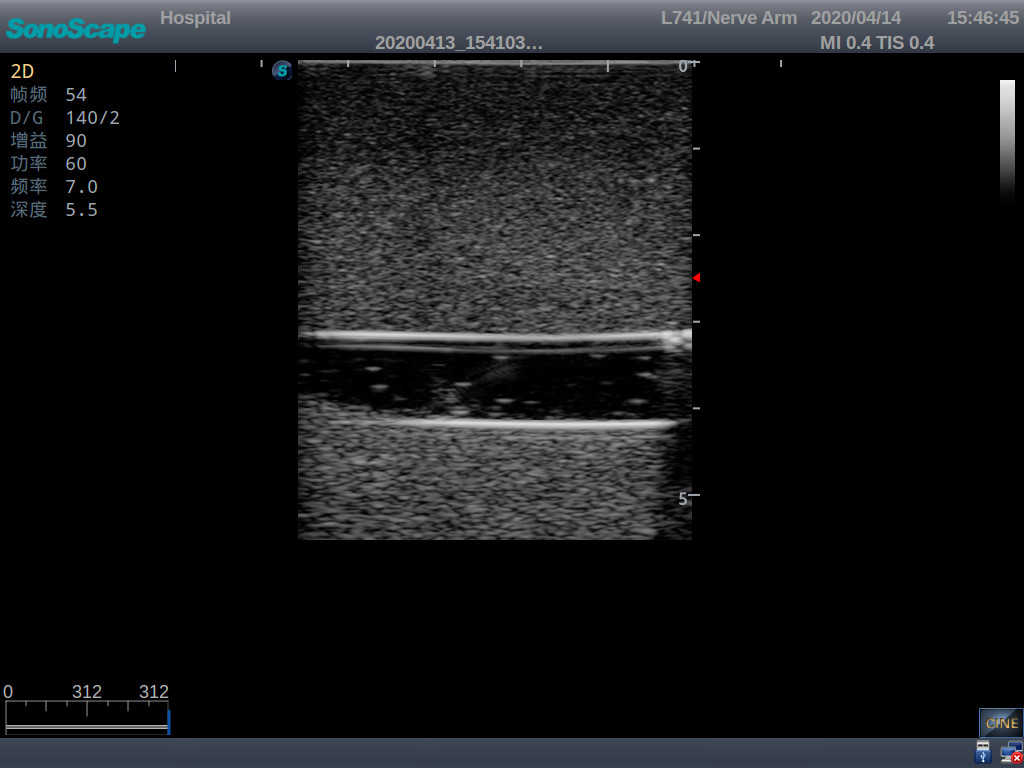

Model TYE1510.1

It is a model covering up from lobulus auriculae plane to the umbilical plane, and it has anatomical structures like clavicle, rib, sternocleidomastoid, jugular vein and basilic vein.

1)   Made of high molecular polymer ultrasound material, close to the real skin

2)   It can be used by real ultrasound machines

3)   Clear and real images of the tissues and organs (basilic vein and superior vena cava)

5)   Observe the guide wire marches

6)   Detect whether the catheter is properly placed